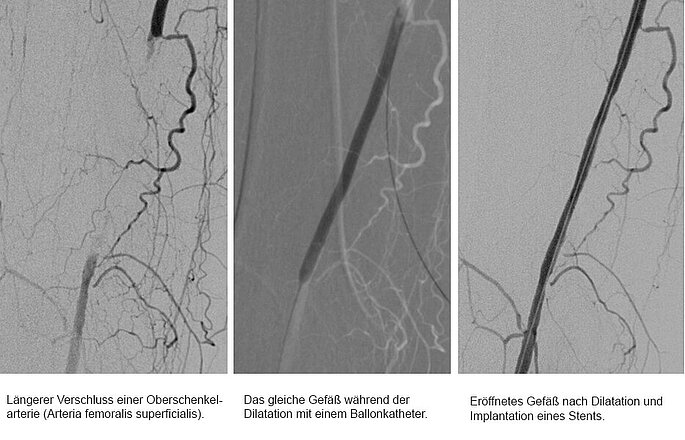

Entscheidet sich der Patient letztendlich für den minimal-invasiven Gefäßeingriff, führen Dr. Merget und seine Kollegen der Radiologie die sogenannte Angioplastie durch. Nachdem die Problemstelle dargestellt wurde, führen sie über die Leistenarterie einen Draht in das betroffene Gefäß ein. Um den Verschluss überwinden zu können, erstellen sie eine „Roadmap“ des Problembereichs. Haben sie die Problemstelle mit dem Draht passiert und sind sie wieder im plaquefreien Teil des Gefäßes angelangt, wird ein Ballonkatheter hinterhergeschoben. Der Ballon wird an der Problemstelle platziert und aufgepumpt (dilatieren). Dabei kommt je nach Gefäß und Katheter ein Druck von bis zu 18 bar zum Einsatz. Zum Vergleich: Einen Autoreifen befüllt man in der Regel mit 2,0 bis 2,5 bar. „Normalerweise halten wir den Druck circa zwei Minuten lang aufrecht. Danach lassen wir den Druck ab und schauen uns das Gefäß an. Ist der Gefäßdurchschnitt ausreichend weit und die Gefäßwand glatt, dann waren wir bereits erfolgreich. Die Plaques wurden an der Wand festgedrückt. Ist das Gefäß dagegen noch verengt oder bestehen Verletzungen der Gefäßwand (Dissektionen), die den Blutstrom noch begrenzen, wird die Prozedur meistens noch einmal wiederholt, ggf. über einen längeren Zeitraum als zuvor“, erklärt Dr. Merget das Vorgehen. Ist auch nach wiederholtem Dilatieren kein zufriedenstellendes Ergebnis erzielt worden, kann ein Stent - ein Gitterröhrchen zur langfristigen Wandstabilisierung - eingesetzt werden. Je nach Gefäßregion kann es auch sinnvoll sein, gleich einen Stent zu implantieren. In sehr beweglichen Körperregionen, wie z. B. dem Kniegelenk, versucht man dagegen, soweit wie möglich auf einen Stent zu verzichten. Schließlich ist das Risiko, dass er dort bricht, leicht erhöht.